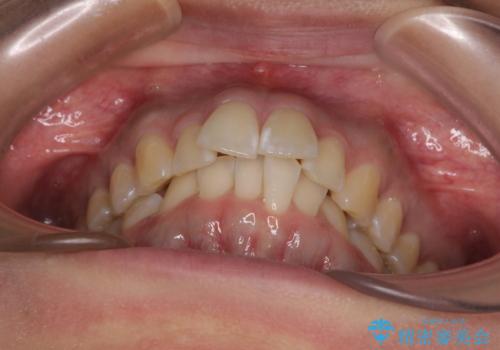

前に飛び出して目立っている前歯を整える インビザライン矯正治療

- 前方に主張した前歯2本を気にして来院された患者様です。

下顎前歯がデコボコしており、その影響で上顎前歯が前方に押し出されている状態でした。

口元が閉じにくいという印象はなかったため、非抜歯矯正にて歯列を整えていくこととしました。

上下左右の親知らずを抜歯し、上下ともに歯列を後方と側方に拡大し、口元を突出させることなくデコボコを解消することとしました。

前歯の形が台形であり、歯列が整ったところでブラックトライアングルが目立つ仕上がりとなったため、IPR(歯と歯の間を削る処置)によって歯の形態を修正し、隙間の目立たない歯列に仕上げることができました。